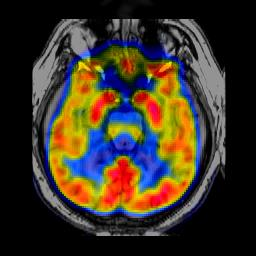

In image fusion, images obtained from different sensors are fused to generate a single image with enhanced information. In recent years, state-of-the-art methods have adopted Convolution Neural Networks (CNNs) to encode meaningful features for image fusion. Specifically, CNN-based methods perform image fusion by fusing local features. However, they do not consider long-range dependencies that are present in the image. Transformer-based models are designed to overcome this by modeling the long-range dependencies with the help of self-attention mechanism. This motivates us to propose a novel Image Fusion Transformer (IFT) where we develop a transformer-based multi-scale fusion strategy that attends to both local and long-range information (or global context). The proposed method follows a two-stage training approach. In the first stage, we train an auto-encoder to extract deep features at multiple scales. In the second stage, multi-scale features are fused using a Spatio-Transformer (ST) fusion strategy. The ST fusion blocks are comprised of a CNN and a transformer branch which capture local and long-range features, respectively. Extensive experiments on multiple benchmark datasets show that the proposed method performs better than many competitive fusion algorithms. Furthermore, we show the effectiveness of the proposed ST fusion strategy with an ablation analysis. The source code is available at: https://github.com/Vibashan/Image-Fusion-Transformer.